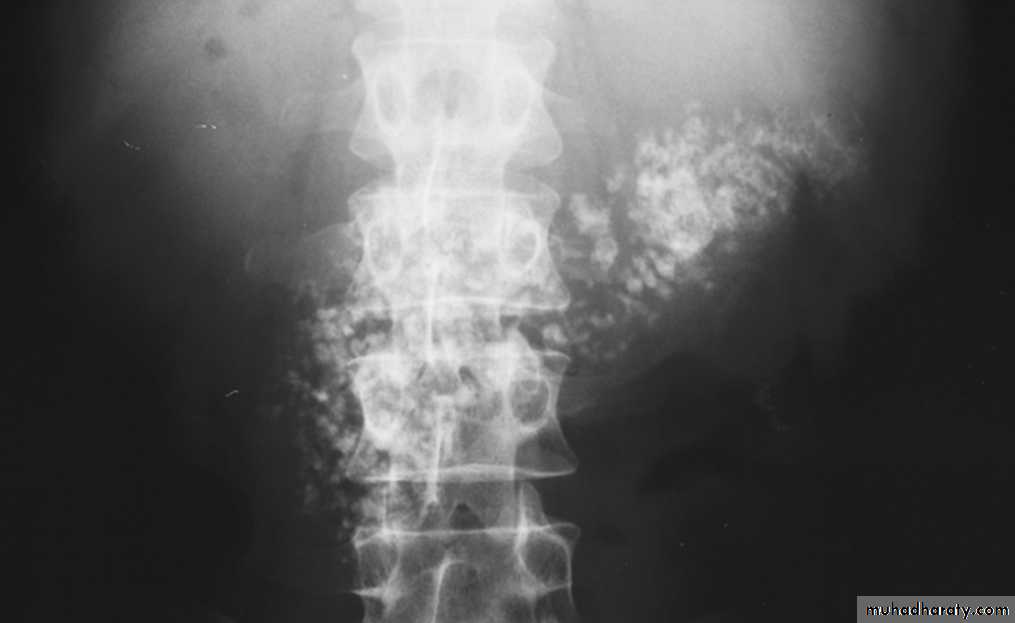

1: xray

SENTINEL LOOP SIGN

COLON CUT-OFF SIGN

Pancreatic calcifications